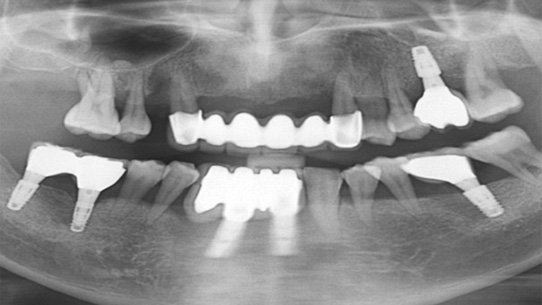

타 치과 에서 6개 치아를 발치하고 12개 임플란트 식립을 진단받고 내원. 고운미소에서 치주치료를 통하여

치아를 보존 시키고 6개의 임플란트 식립한케이스

잇몸뼈가 녹아내려 다른 병원에서 임플란트 12개 진단을 받고 내원, 고운미소에서 치주치료를 시행한 결과 전치부 잇몸이 개선되어 발치 하지 않고

크라운으로 수복하였고, 어금니에 6개의 임플란트를 식립하였습니다.